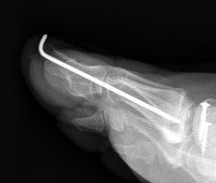

+/- intramedullary device

Stryker SmartToe IM device ToeGrip